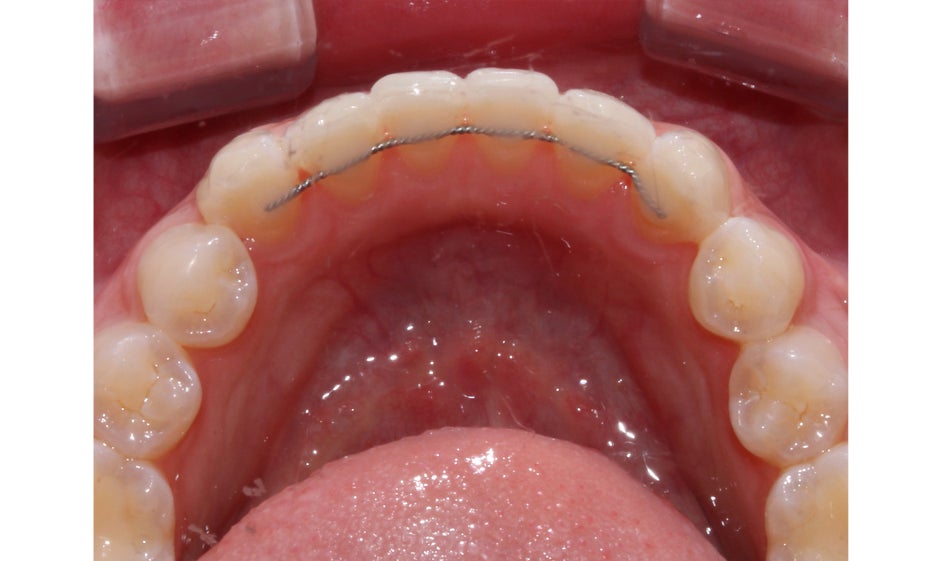

뻐드렁니교정 후 상악 교합면을 보면

서로 겹쳐져 있던 중절치가 가지런하게

배열된 것을 확인할 수 있는데요,

전체적인 안모의 형태도 이상적인

U-라인으로 바뀌어 정돈된 느낌입니다.

하악의 경우 전치부의 Crowding으로 인해

삐뚤거렸던 치열이 가지런하게 바뀐 모습입니다.